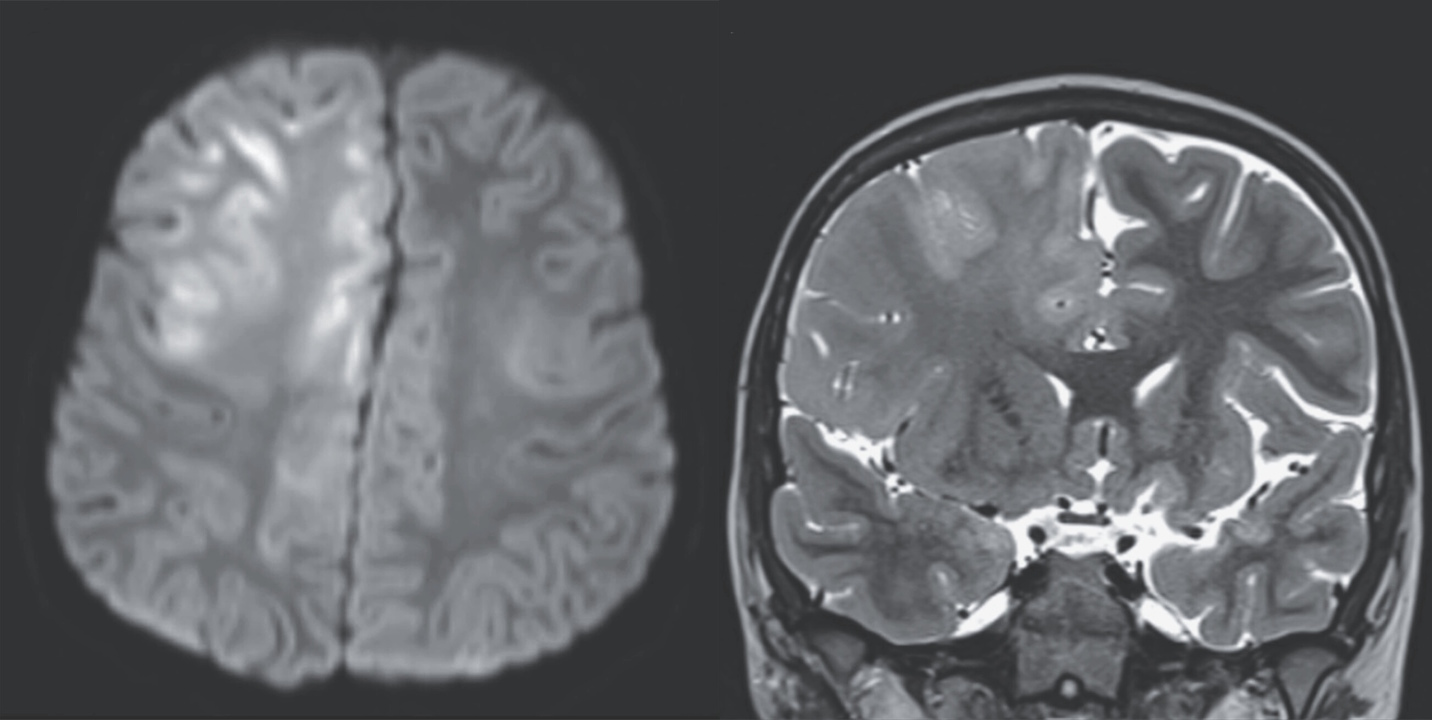

Набряк мозку на знімках магнітно-резонансної томографії голови хлопчика. Kung & Crawford / The New England Journal of Medicine, 2026

До педіатрів звернулися батьки семирічного хлопчика, у якого протягом останніх трьох місяців почали погіршуватися розумові здібності та з’явилися судоми. Під час обстеження лікарі виявили у нього надмірні прояви рефлексів і клонус — мимовільні ритмічні скорочення та розслаблення м’язів, окрім цього хлопчик не говорив. Магнітно-резонансна томографія мозку вказала на набряк у лобній частці кори та мозолистому тілі, а електроенцефалографія — на високочастотні спалахи мозкової активності.